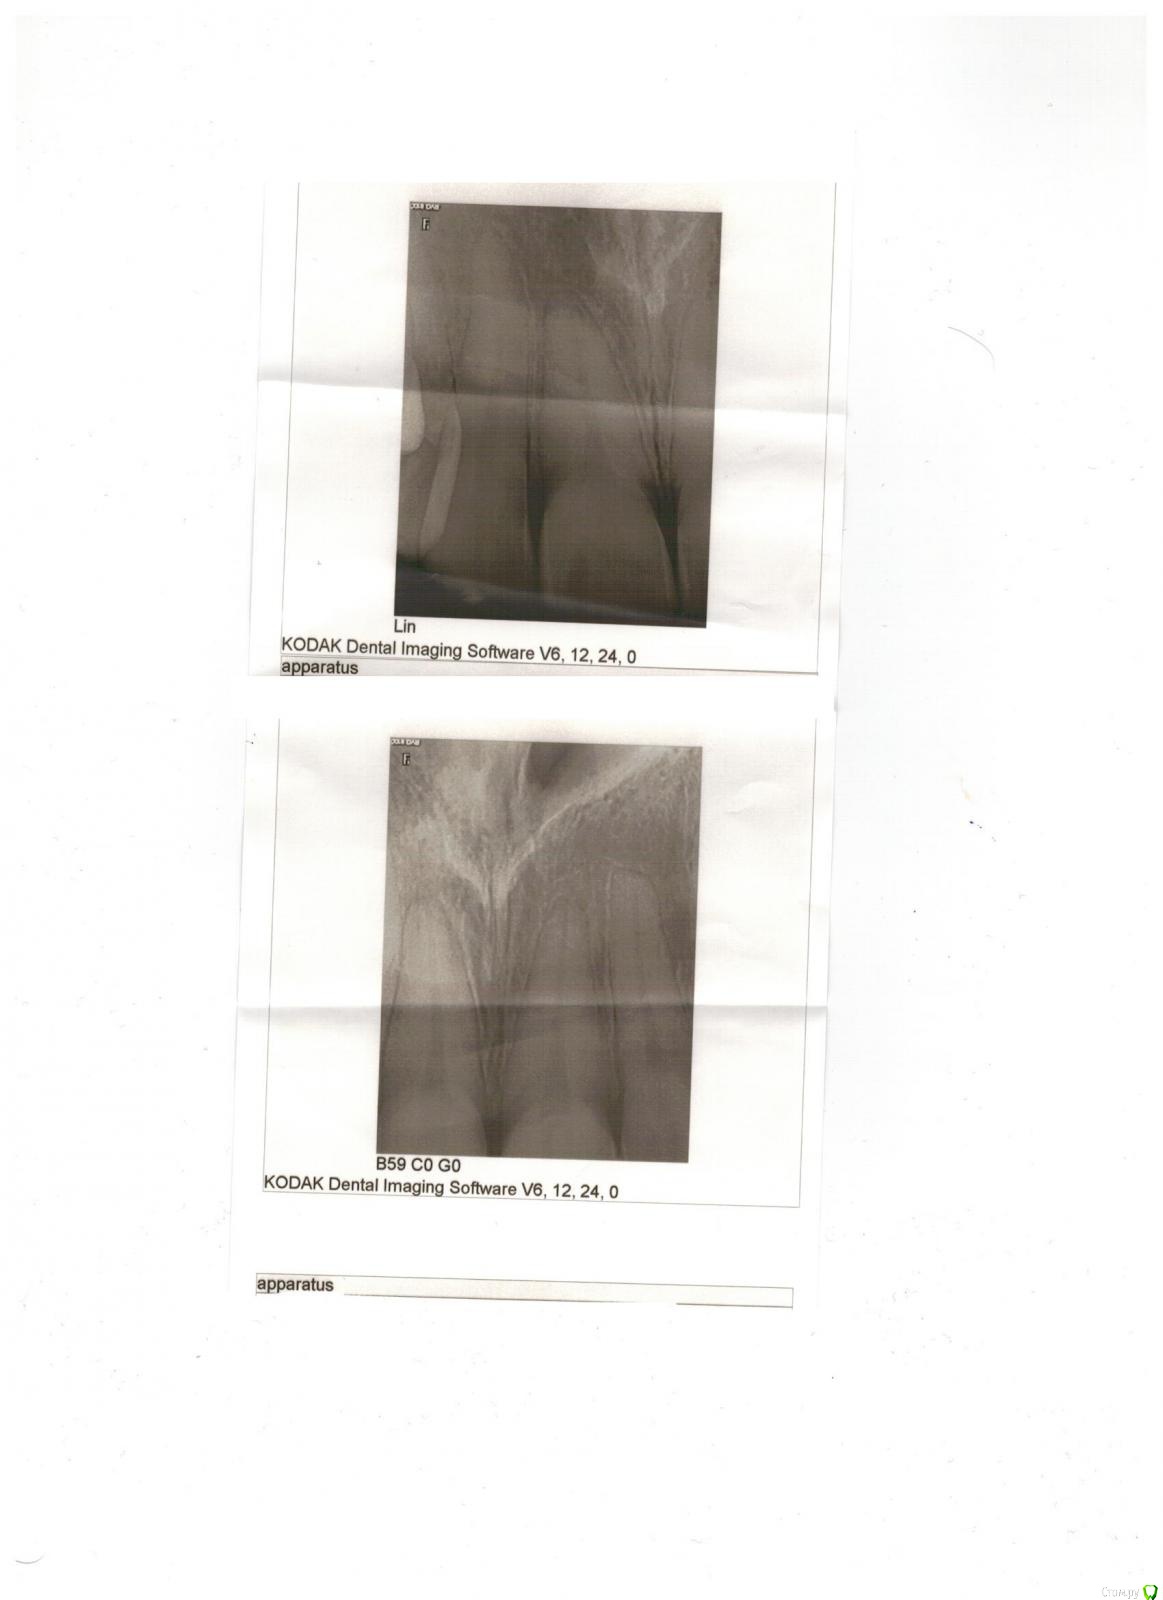

Александр К Опубликовано 8 февраля, 2016 Поделиться Опубликовано 8 февраля, 2016 Добрый день! С супругой произошла неприятность, подскользнулась, получила травму - удар в область передних верхних зубов. Удар был не сильный, даже ни опухоли, ни синяка, ни разбитой губы, но... Шатаеся один зуб уже неделю, чуть болит. После похода в гос и частную клинику совершенно разные вердикты, причем в частной вообще жуть: по томографии врач сказал, что откололась часть кости к которой крепится зуб и теперь его надо удалять, вшивать "новую" кость, ходить пять дней без зуба, потом пол года с элементом вставной челюсти, потом вставлять корень и новый зуб. Все бы ничего, но зуб то вроде целый и для девочки это все ой как не приятно и сложно, да и дорого что тут греха таить.Загуглив я сделал вывод что это перелом альвеолярного отростка верхней челюсти, пишут что установкой шины можно это вылечить. Жалко вот так вот терять здоровый зуб.Теперь о гос поликлинике: врач сделала рентген и указала на перелом корня, хотя врач из частной клиники перелома не увидел. В общем кому верить и что делать не знаем. Пойдем к третьему врачу, но хотелось бы послушать мнение профессионалов со стороны. Буду благодарен любому ответу, спасибо! Ссылка на комментарий

Александр К Опубликовано 8 февраля, 2016 Автор Поделиться Опубликовано 8 февраля, 2016 снимки Ссылка на комментарий